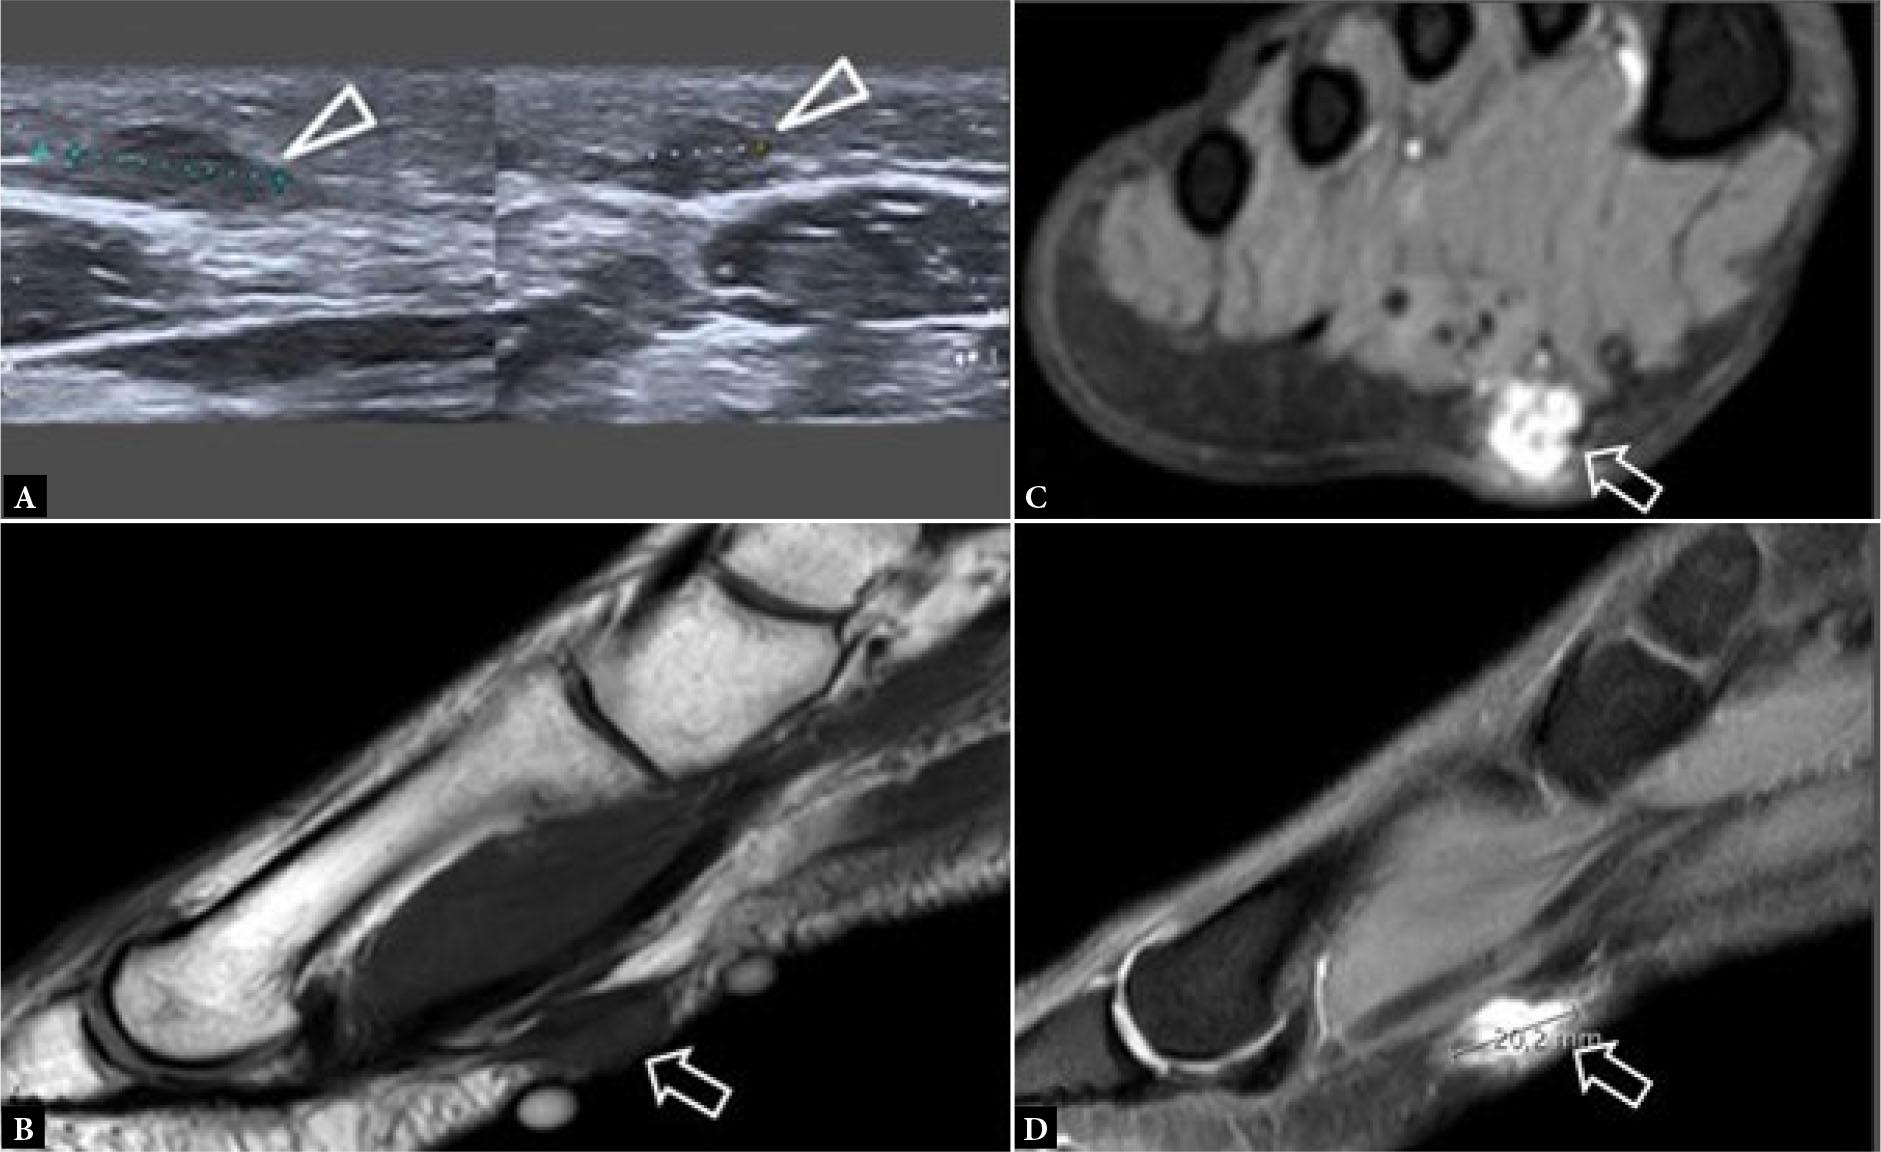

Lesser MTP joint plantar plate tear

Even more so than the 1st MTP joint, the plantar plates of the lesser MTP joints resist joint hyperextension and provide sagittal stability(11). Distally, the plantar plates are firmly attached to the proximal phalangeal bases while proximally, they are loosely attached to the metacarpal necks by fibro-synovial tissue(12). On either side, the plantar plates are firmly attached to the medial and lateral accessory collateral ligaments (Fig. 13) and, as such, co-existent injury of the plantar plate and accessory ligaments commonly occurs(12). Plantar plate tear can lead to MTP joint medial or lateral deviation, dorsal subluxation, and hammer toe(13). The normal plantar plate and plate tears are shown on US and MRI in Fig. 14 and Fig. 15. As with the 1st MTP joint, a midline hyperintense zone, measuring up to 2.5 mm long, at the phalangeal base is a normal anatomic recess(11) (Fig. 10). This is less frequently appreciated on US as a hyperechoic zone.

Fig. 14.

31–year-old female professional basketball player with forefoot pain. A, B. Consecutive longitudinal greyscale US images shows moderately thickened plantar plate (arrowheads) of the 2nd MTP joint with a long intrasubstance tear (short arrows). C. Transverse greyscale US image shows moderate pericapsular fibrosis (long arrow) inferolateral to the 2nd MTP joint. D. Longitudinal greyscale US image of the asymptomatic normal contralateral 2nd MTP joint plantar plate for comparison. (images courtesy of Dr James Linklater)

Fig. 15.

Same patient as previous figure. Sagittal A. proton density (PD) and B. T2W FS images shows a moderately thickened plantar plate (arrowheads) of 2nd MTP joint with intrasubstance tear (short arrow). C, D. Coronal T2W fat-suppressed MR images shows moderate-severity reactive pericapsular fibrosis (long arrow) inferolateral to the 2nd MTP joint with moderate pericapsular inflammation (open arrowheads). The plantar plate tear was confirmed and treated surgically, with subsequent return to sports (images courtesy of Dr James Linklater)

The 2nd, followed by the 3rd, MTP joint plantar plates are the most frequently injured(12). Plantar plate tears typically occur at the junction between the plantar plate and the accessory collateral ligament close to the phalangeal attachment, most commonly at the inferolateral aspect of the joint (Fig. 13). On US, most plantar plate tears are seen as discrete partial or full thickness hypoechoic defects in the plate substance(13,14). Flattening or attenuation may occur with plantar plate degeneration. When the plantar plate is completely torn, the flexor digitorum tendon may directly contact the metatarsal head(13,14). In the chronic setting, reactive pericapsular fibrosis can be seen as a non-compressible hypoechoic cuff of tissue abutting the plantar and inferolateral (or inferomedial) aspects of the MTP joint(13,14). US should be performed in both longitudinal and transverse planes, scanning the plantar aspect of the MTP joint slowly from lateral to medial and from distal to proximal, with angling of the transducer to avoid anisotropy. Most injuries occur at the distal attachment of the plate. Longitudinal US is best to detect and characterize tears while transverse US is useful to delineate the eccentric location of pericapsular fibrosis and to exclude subluxation of the flexor digitorum tendon. Longitudinal US during toe dorsiflexion can improve tear detection and appreciation of MTP joint subluxation(14).

For MR imaging, T1-weighted (T1W) coronal images are usually the most helpful as routine sagittal forefoot images do not always image the plantar plate in a true sagittal plane(12) (Fig. 15). Performing MRI in the prone position, with the foot in plantarflexion, results in less magic angle artifact and less movement artefact potentially facilitating assessment of the plantar plate(11). Prone positioning also leads to slight plantar shift of the interdigital soft tissues improving assessment of Morton’s neuroma(15). Dynamic US assessment during MTP joint dorsiflexion or during dorsal drawer (Lachman) testing can help assessment of plantar plate integrity and MTP joint stability. Compared with surgical findings, the pooled sensitivity (93%) of US for detecting plantar plate tears is comparable to that of MRI (89–95%), though MRI has a higher specificity (54–83%) than US (33–52%)(16). A negative US examination makes plantar plate injury very unlikely. If US is positive or equivocal, MRI can provide more specificity as to the nature of the injury and yield a more global assessment of the MTP joint(17).